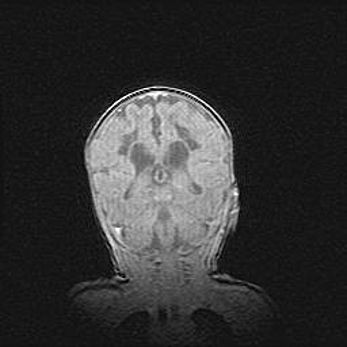

Открытая гидроцефалия.

Возраст: 6 месяцев 15 дней

Вес: 6200 г

Пол: женский

Окружность головы: 41 см

Срок гестации: 38 недель

Гидроцефалия головного мозга у новорожденных – это скопление избыточного количества цереброспинальной жидкости в головном мозге. Ее избыточное скопление в мозге приводит к патологическому расширению желудочков мозга (четырех полостей, расположенных в глубине белого вещества мозга, заполненных цереброспинальной жидкостью и связанных узкими проходами).

Открытый тип гидроцефалии (сообщающаяся) наблюдается тогда, когда нарушен механизм всасывания ликвора в системный кровоток. При этом типе причиной заболевания чаще всего является перенесенные ранее инфекции (например: менингит),  либо же наличие крови в субарахноидальном пространстве.